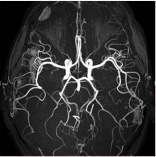

基本的な人間ドックの検査には含まれない脳疾患も徹底チェック!

基本的な人間ドックの検査には含まれない脳疾患も徹底チェック!

3テスラのMRIなど大学病院クラスの設備と各分野の専門医師が様々な疾患を見逃さない体制

3テスラのMRIなど大学病院クラスの設備と各分野の専門医師が様々な疾患を見逃さない体制

日本人の死亡原因は1位がん 2位心疾患 3位脳疾患です。そして多くの疾患は早期発見、早期治療が何よりも大切です。『林脳神経外科メディカルクリニック』では、大学病院クラスの高性能な医療設備を導入すると共に、各分野の専門医師を集結させ、様々な疾患の早期発見、早期治療を目指しています。

頭部MRI 頭部MRI

|

|

検査画像のダブルチェック

画像検査の見落としがないよう各科専門の医師による確認後、読影専門医による画像確認のダブルチェックを実施しております。

頭部MRIは、脳神経外科の専門医がチェックします。